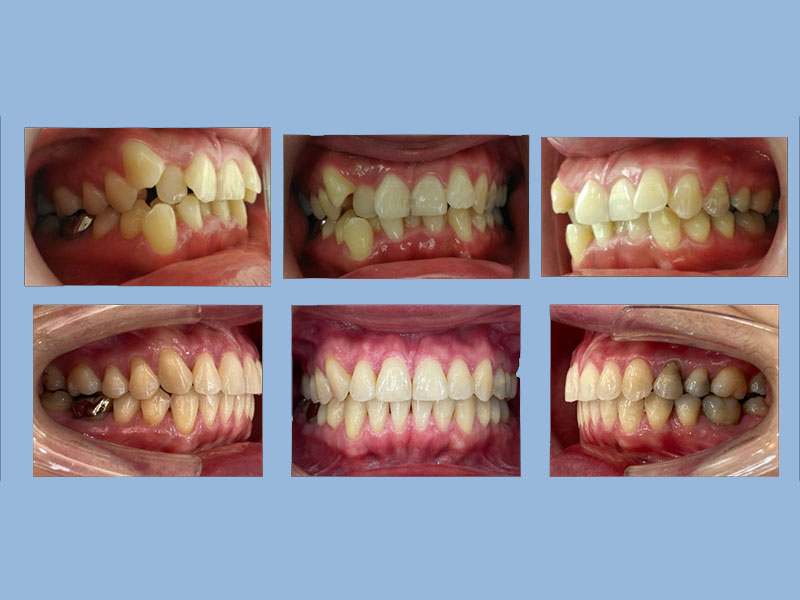

蕭先生 (22歲) 矯正完成

狀態:亂、擠、錯咬、牙周病、沒拔牙